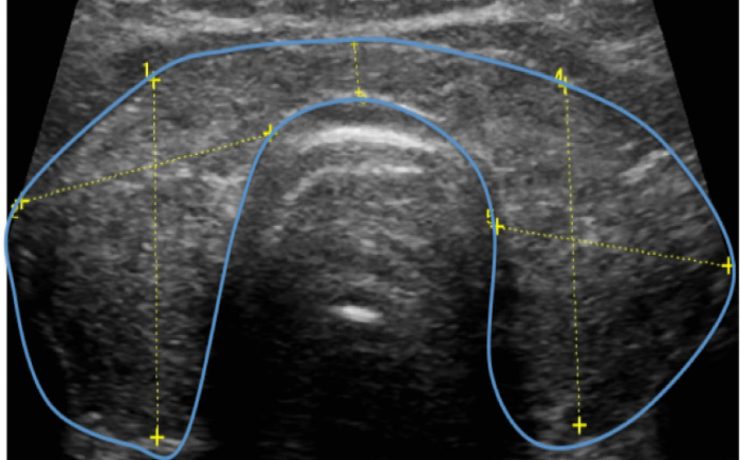

El nódulo tiroideo, es una entidad patológica muy frecuente, con una prevalencia estimada de 4 a 7% por palpación en relación 5:1 en mujeres. Un nódulo tiroideo de más de 1 cm de diámetro por lo general es palpable. Sin embargo, la detección de un nódulo por palpación dependerá de